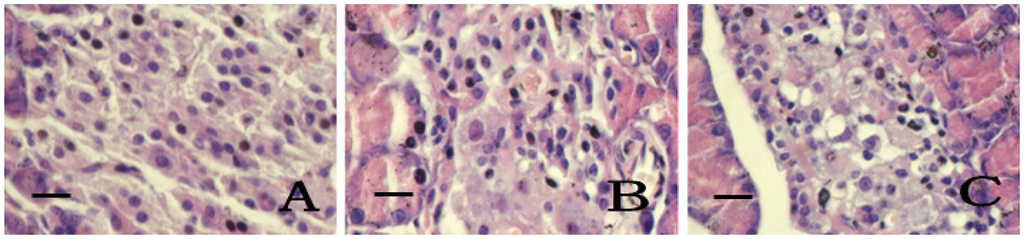

2.5. Pancreatic Islets Tissue Pathology